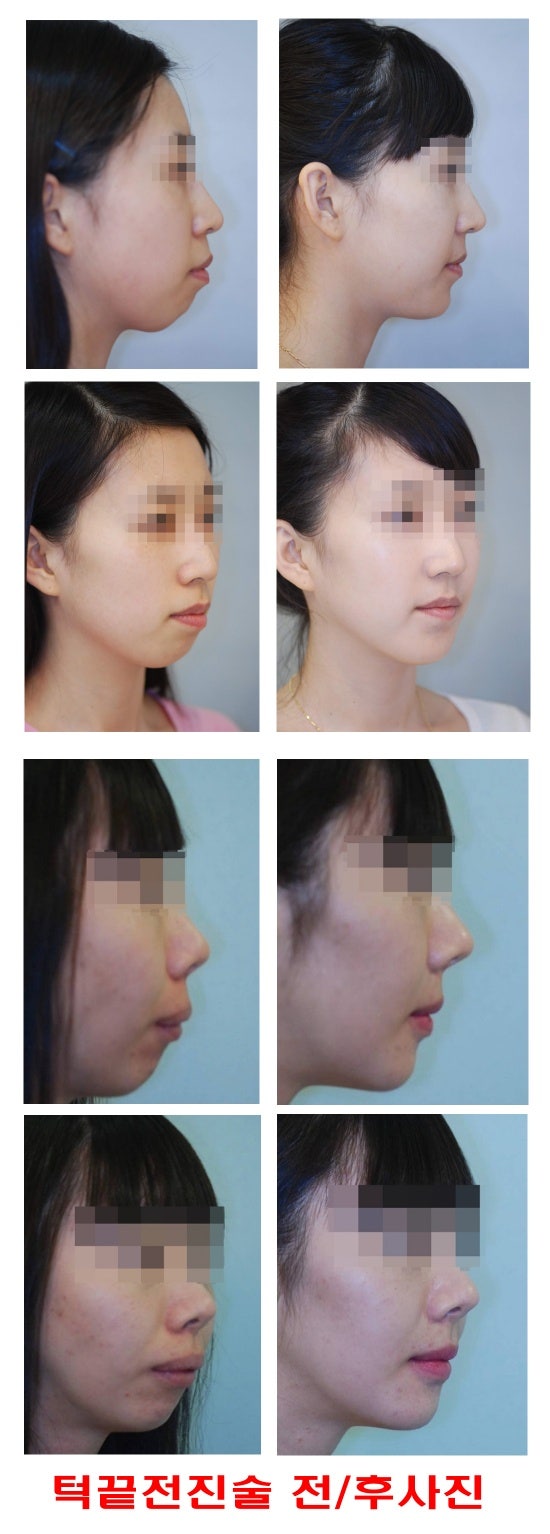

턱끝전진술 돌출입이랑 무턱때문에 교정을 예전에 했었는데 인중이 짧고 무턱도 많이 나아지진

《※무턱 수술 전후 사진 보기※》